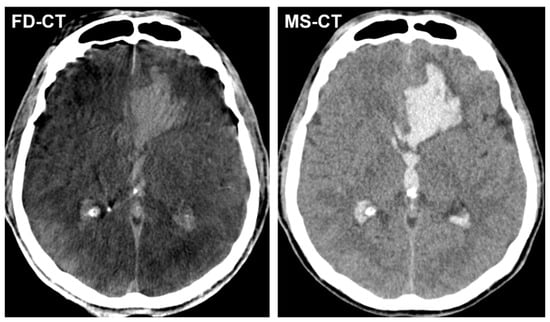

Clinical Comparison of FD-CT and MS-CT in Aneurysmal Subarachnoid Haemorrhage: A Single Center Experience

3.3.1. Blood Distribution